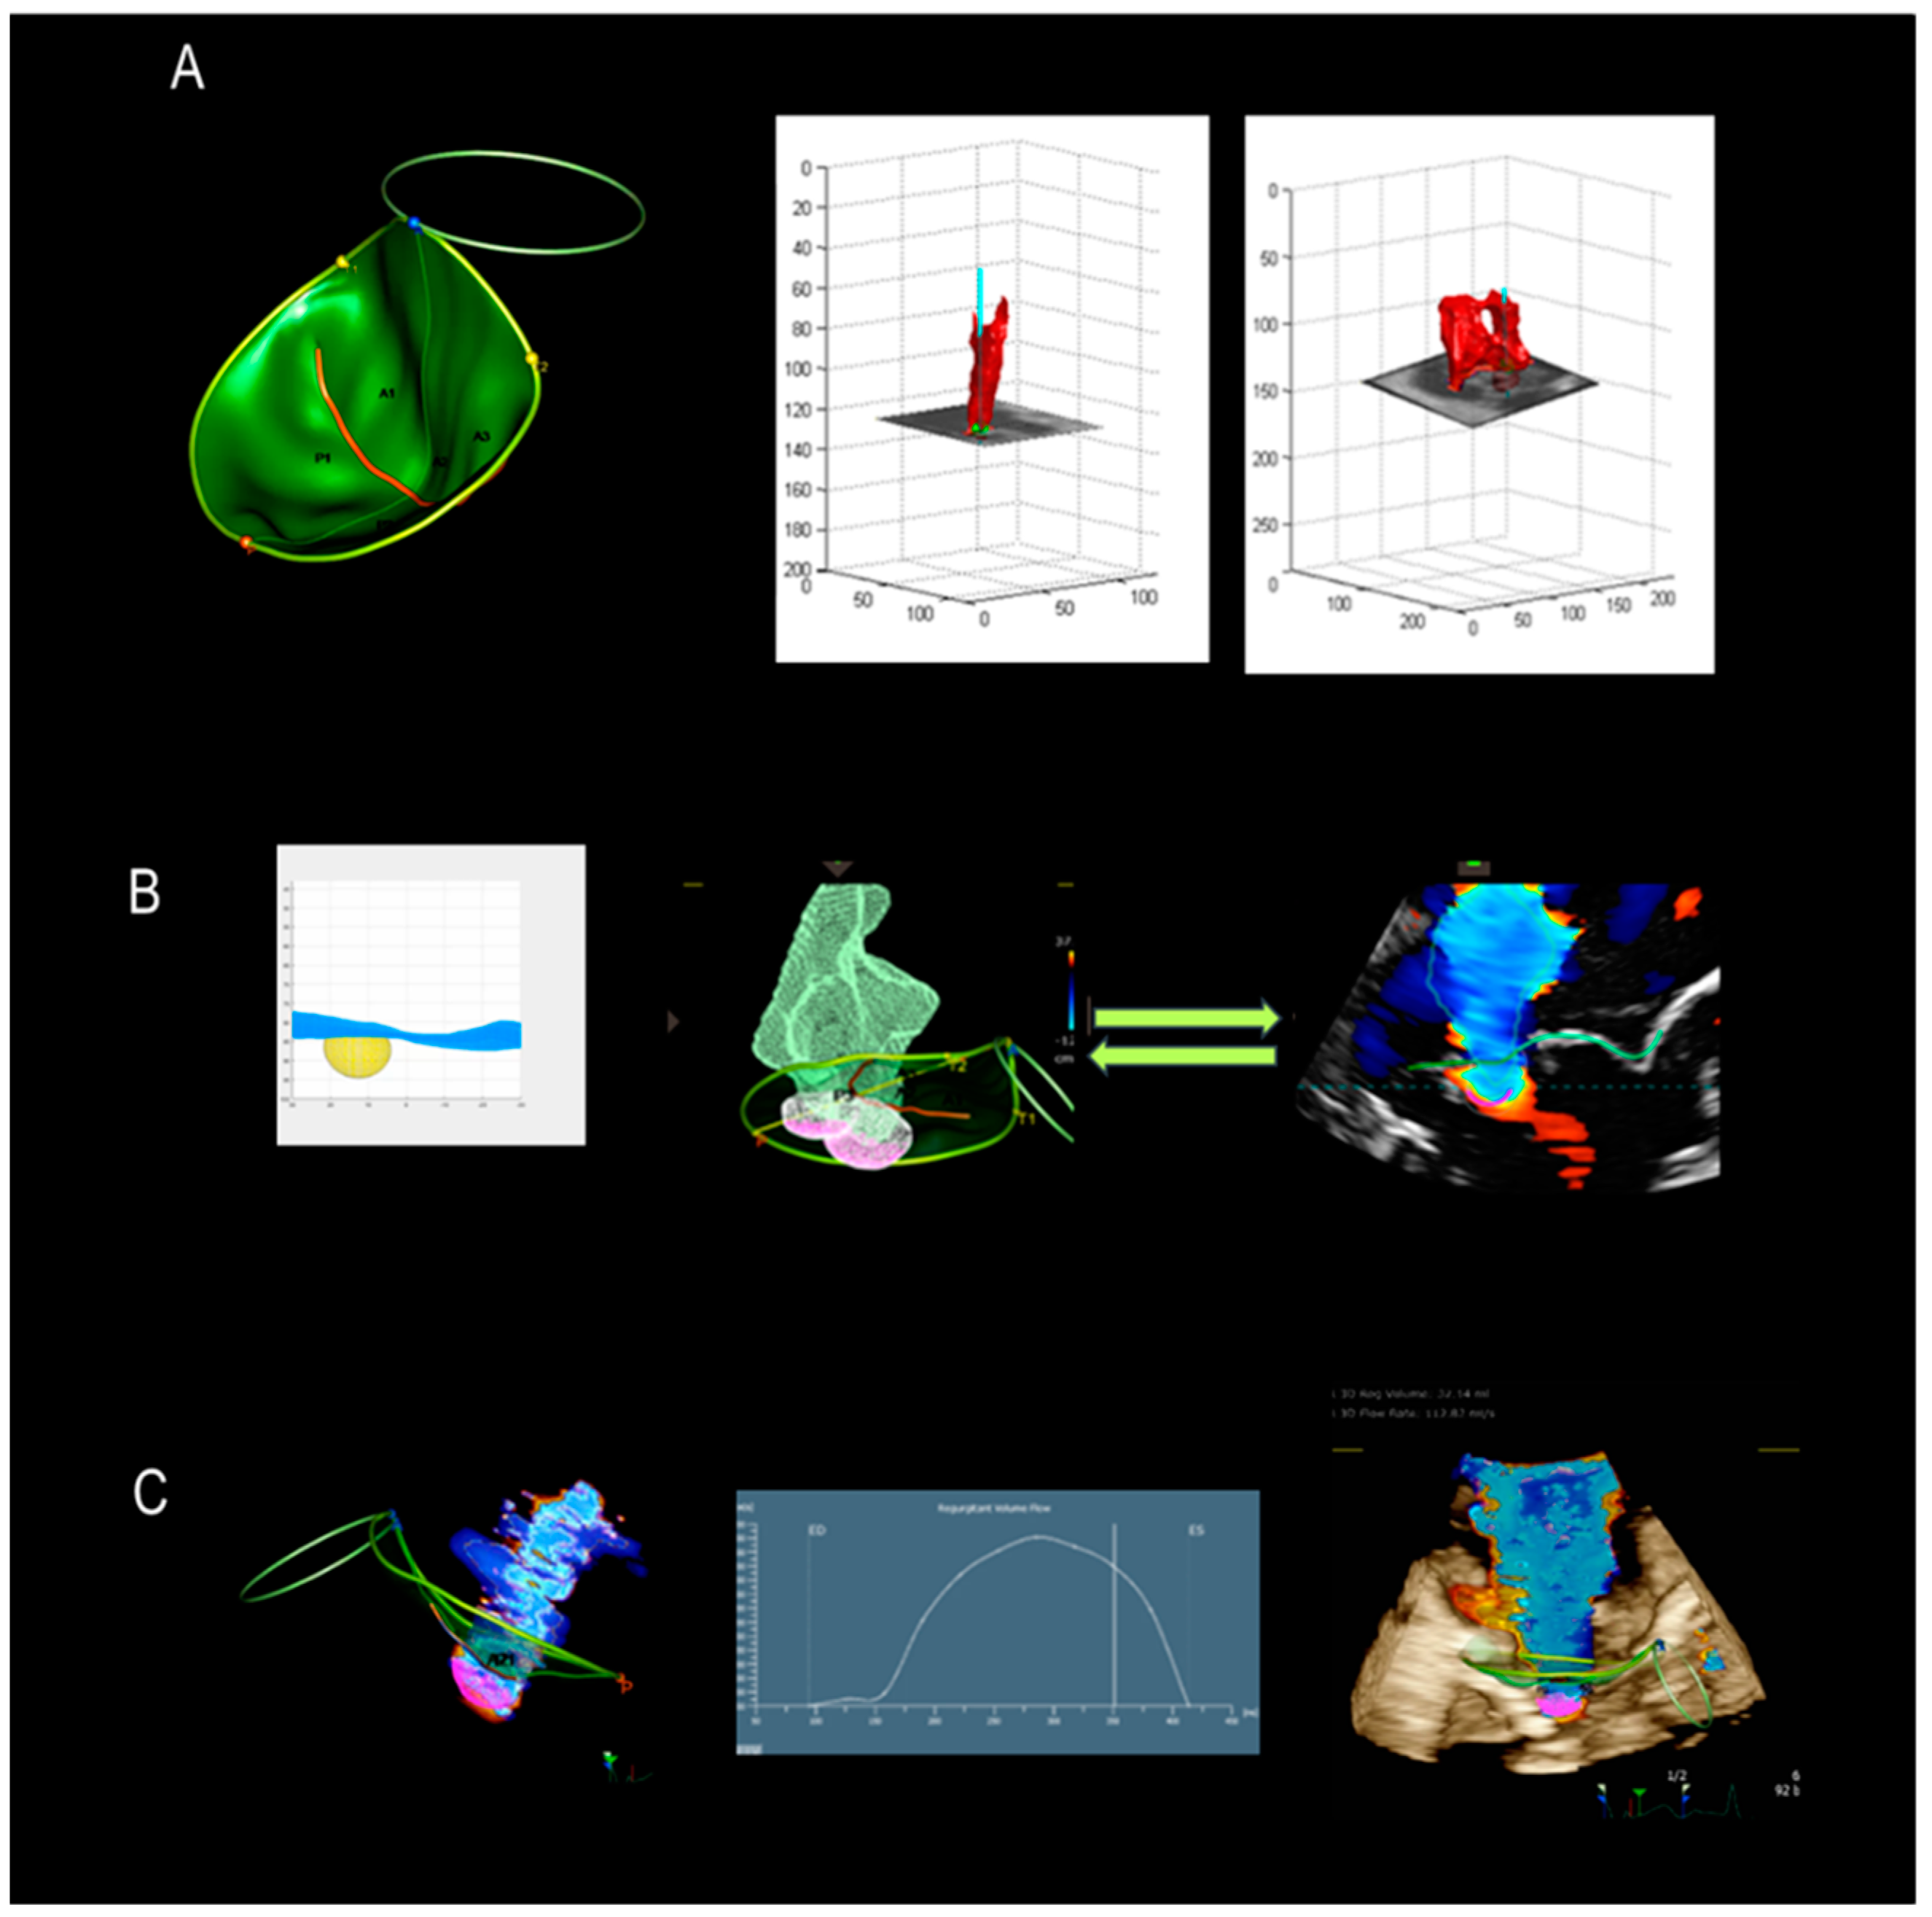

4. New Technologies

4.1. Photorealistic Vision and Transparency

4.2. Surface Rendering

5. Assessment of Regurgitation Severity

Current Modalities

6. A New Tool

7. New Mini TEE Probe